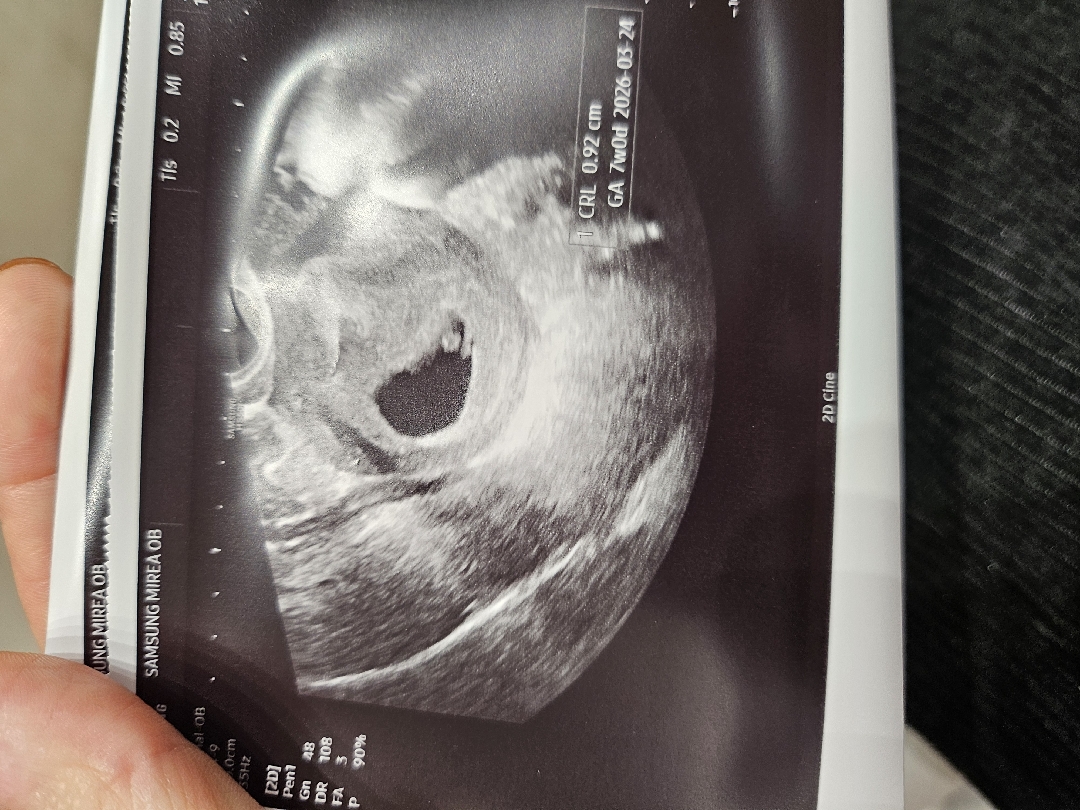

오늘 아기 7주차 확인하고 왔습니당😊 콩알만한 1센치인데도 심장소리 듣는데 벅차더라구요~~ 근데 입덧이 너무심해서 약 타왔어요 먹어도 토하고 울렁울렁 힘없이 누워만있게되고..ㅠㅠ 오늘저녁부터 먹을건데 먹으면서도 내심 맘이 불편하긴한데 입덧스트레스가 더 해롭다는 의사선생님 말씀을듣고 도전하려합니다 ㅠㅠ